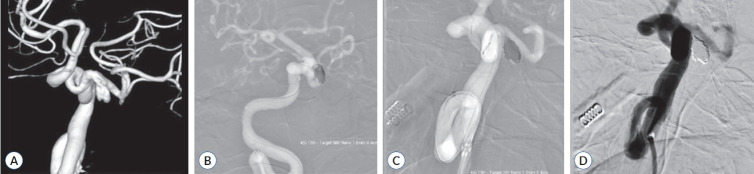

Persistent trigeminal artery (PTA) is the most common residual manifestation of persistent carotid-vertebrobasilar anastomosis, with the medial-type (intrasellar or sphenoidal) PTA being exceptionally rare. Aneurysms originating from the PTA trunk are not common. We present a unique case of an aneurysm located at the trunk of the medial-type PTA in a patient presenting with trigeminal neuralgia who successfully managed by endovascular procedure. Furthermore, we discuss the anatomical features of this aneurysm and relevant reports, and examine the possible pathomechanism of the associated pain.

Abstract Image